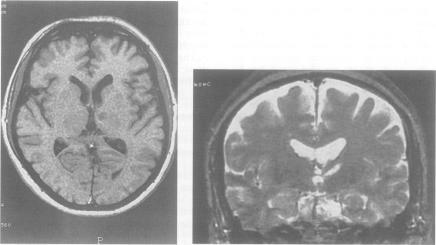

Anomia for proper names after left thalamic infarct.

J Neurol Neurosurg Psychiatry. 1994 Oct;57(10):1283-4. doi: 10.1136/jnnp.57.10.1283.

Persistent pure verbal amnesia and transient aphasia after left thalamic infarction.

J Neurol. 1995 May;242(5):289-94. doi: 10.1007/BF00878870.